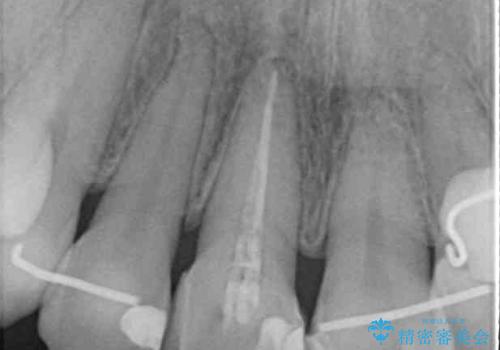

- 前歯の変色を気にして来院された患者様です。

ラミネートベニアによる治療を以前受けていたものの、神経組織が失活して以降、徐々に変色してきたとのことでした。

オールセラミッククラウンにて補綴治療を行うこととしました。